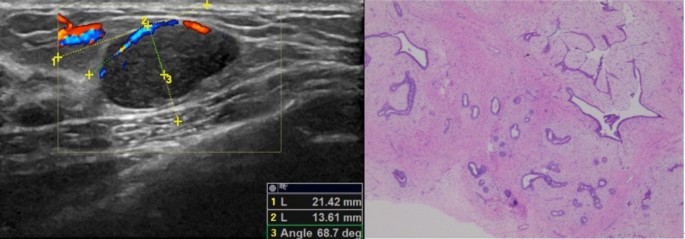

A 26-year-old woman with fibroadenoma of the right breast. (A) The left panel shows the incident angle of the main vessel of the breast nodule is 68.7°; (B) the right panel shows histopathology (HE × 200).